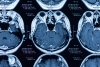

MR da vücudumuzdaki hidrojen protonları uyarılarak sinyal alınır. Sıvı yoğun ortamda hidrojen protonları hareketli olur, bu hareket diffüzyon MR tekniği ile hesaplanır. Tümör dokusu hücreden yoğun olduğu için hidrojen protonlarının hareketliliği kısıtlanır. Bu teknikle tümör tespiti yapılabildiği gibi, iyi huylu kötü huylu tümör ayrımı yapılabilir. Tümör tedavi edildikten sonra içinde doku ölümünden sonra sıvı artışı olur bu da hidrojen protonlarının daha rahat hareket etmesini sağlayarak difüzyon değerlerini değiştirir. Diffüzyon MR tedavi yanıtını belirlemede etkindir. -